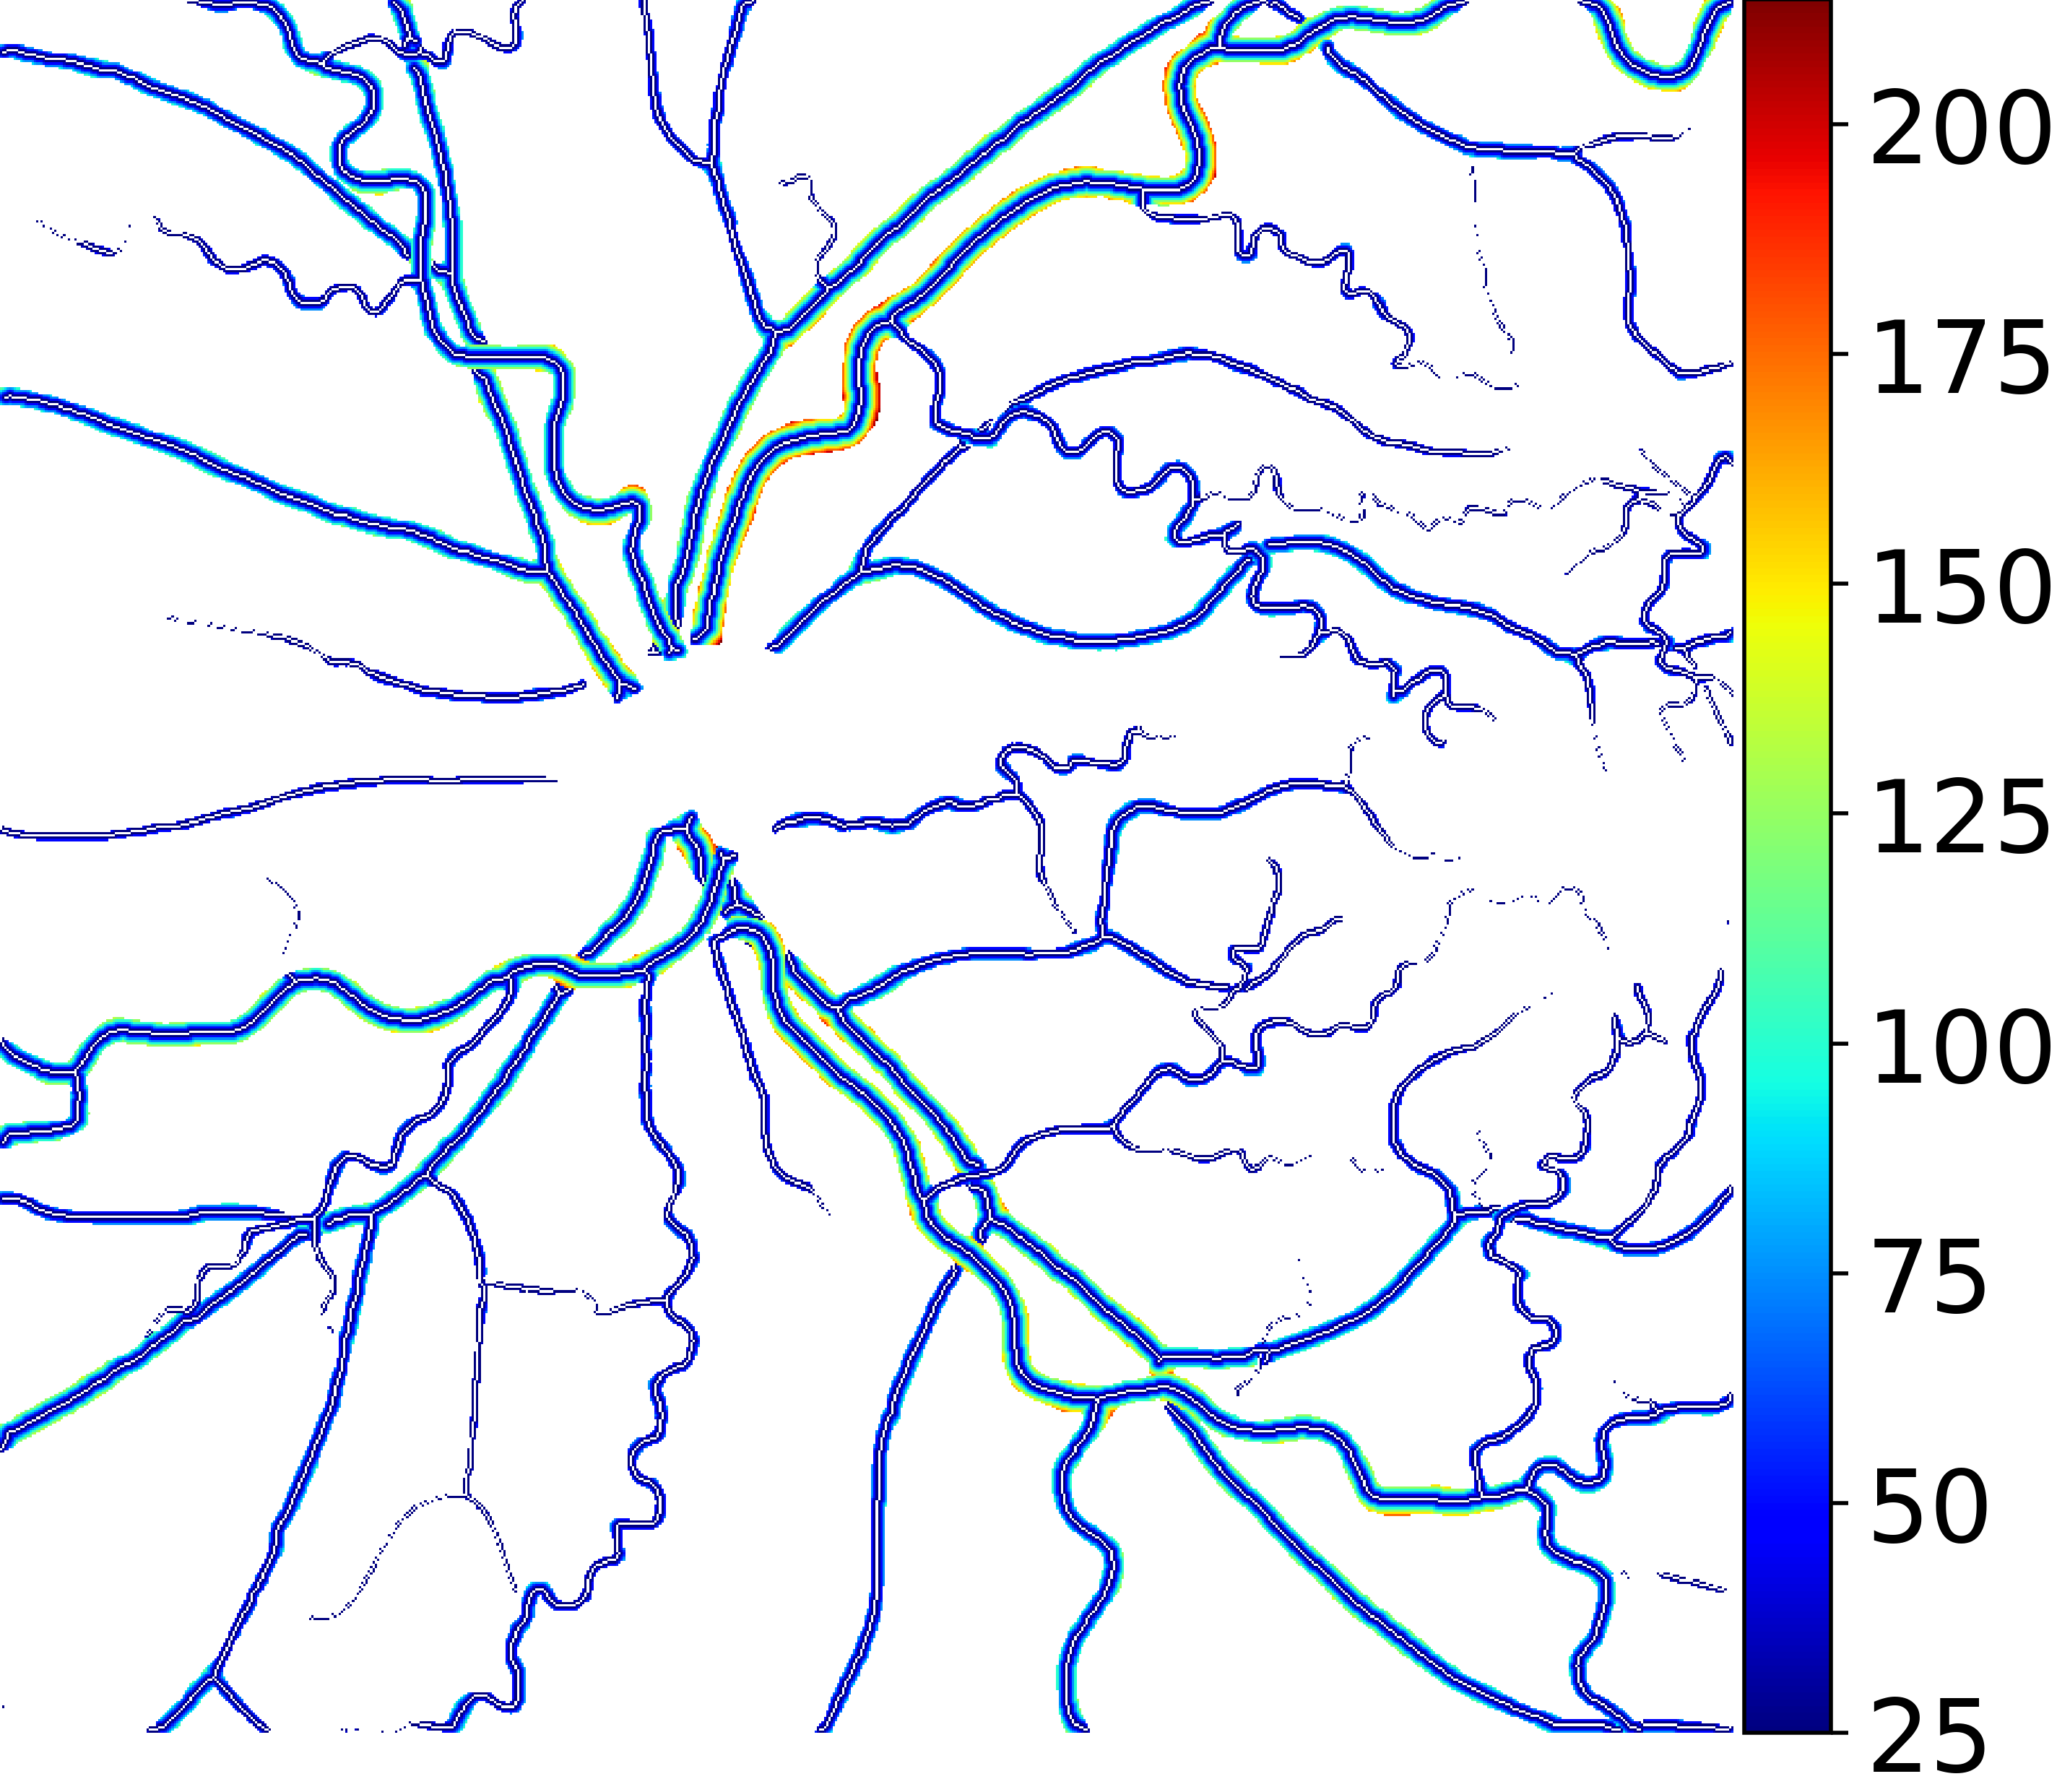

IV-C Vessel Width Estimation

From the segmentation predicted by the SegRAVIR network, our model measures the diameter of the arteries and veins. To this end, the segmentation probability map is first thresholded, using a constant value of 0.5, to obtain the medial curves of the vessels by iteratively identifying and removing border pixels while maintaining vessel connectivity, in an approach similar to the thinning algorithm presented by Zhang et al. [49]. Then, the distance transform of the medial curve mask is multiplied with the segmentation mask in a pixel-wise manner. The result is the diameter distance map with respect to the medial curves of the segmented vessels.

VI-B Vessel Width Estimation

Table VI presents a quantitative comparison of the measured diameters using the segmentation outputs of SegRAVIR and competing approaches. Using the pixel-wise annotated masks, the reference average diameter of the arteries and veins in the test set of the RAVIR dataset were measured as and , respectively. According to our analysis, SegRAVIR can accurately measure the diameter of the vessels and it achieves the smallest MAPE among the competing approaches. Specifically, in comparison to CE-Net, Iter-Net, and DU-Net, respectively, SegRAVIR is on average , and more accurate in terms of MAPE for the measured diameter of arteries and , and in terms of MAPE for the measured diameter of veins. Fig. 6 presents qualitative comparisons of reference and SegRAVIR estimated diameter maps.